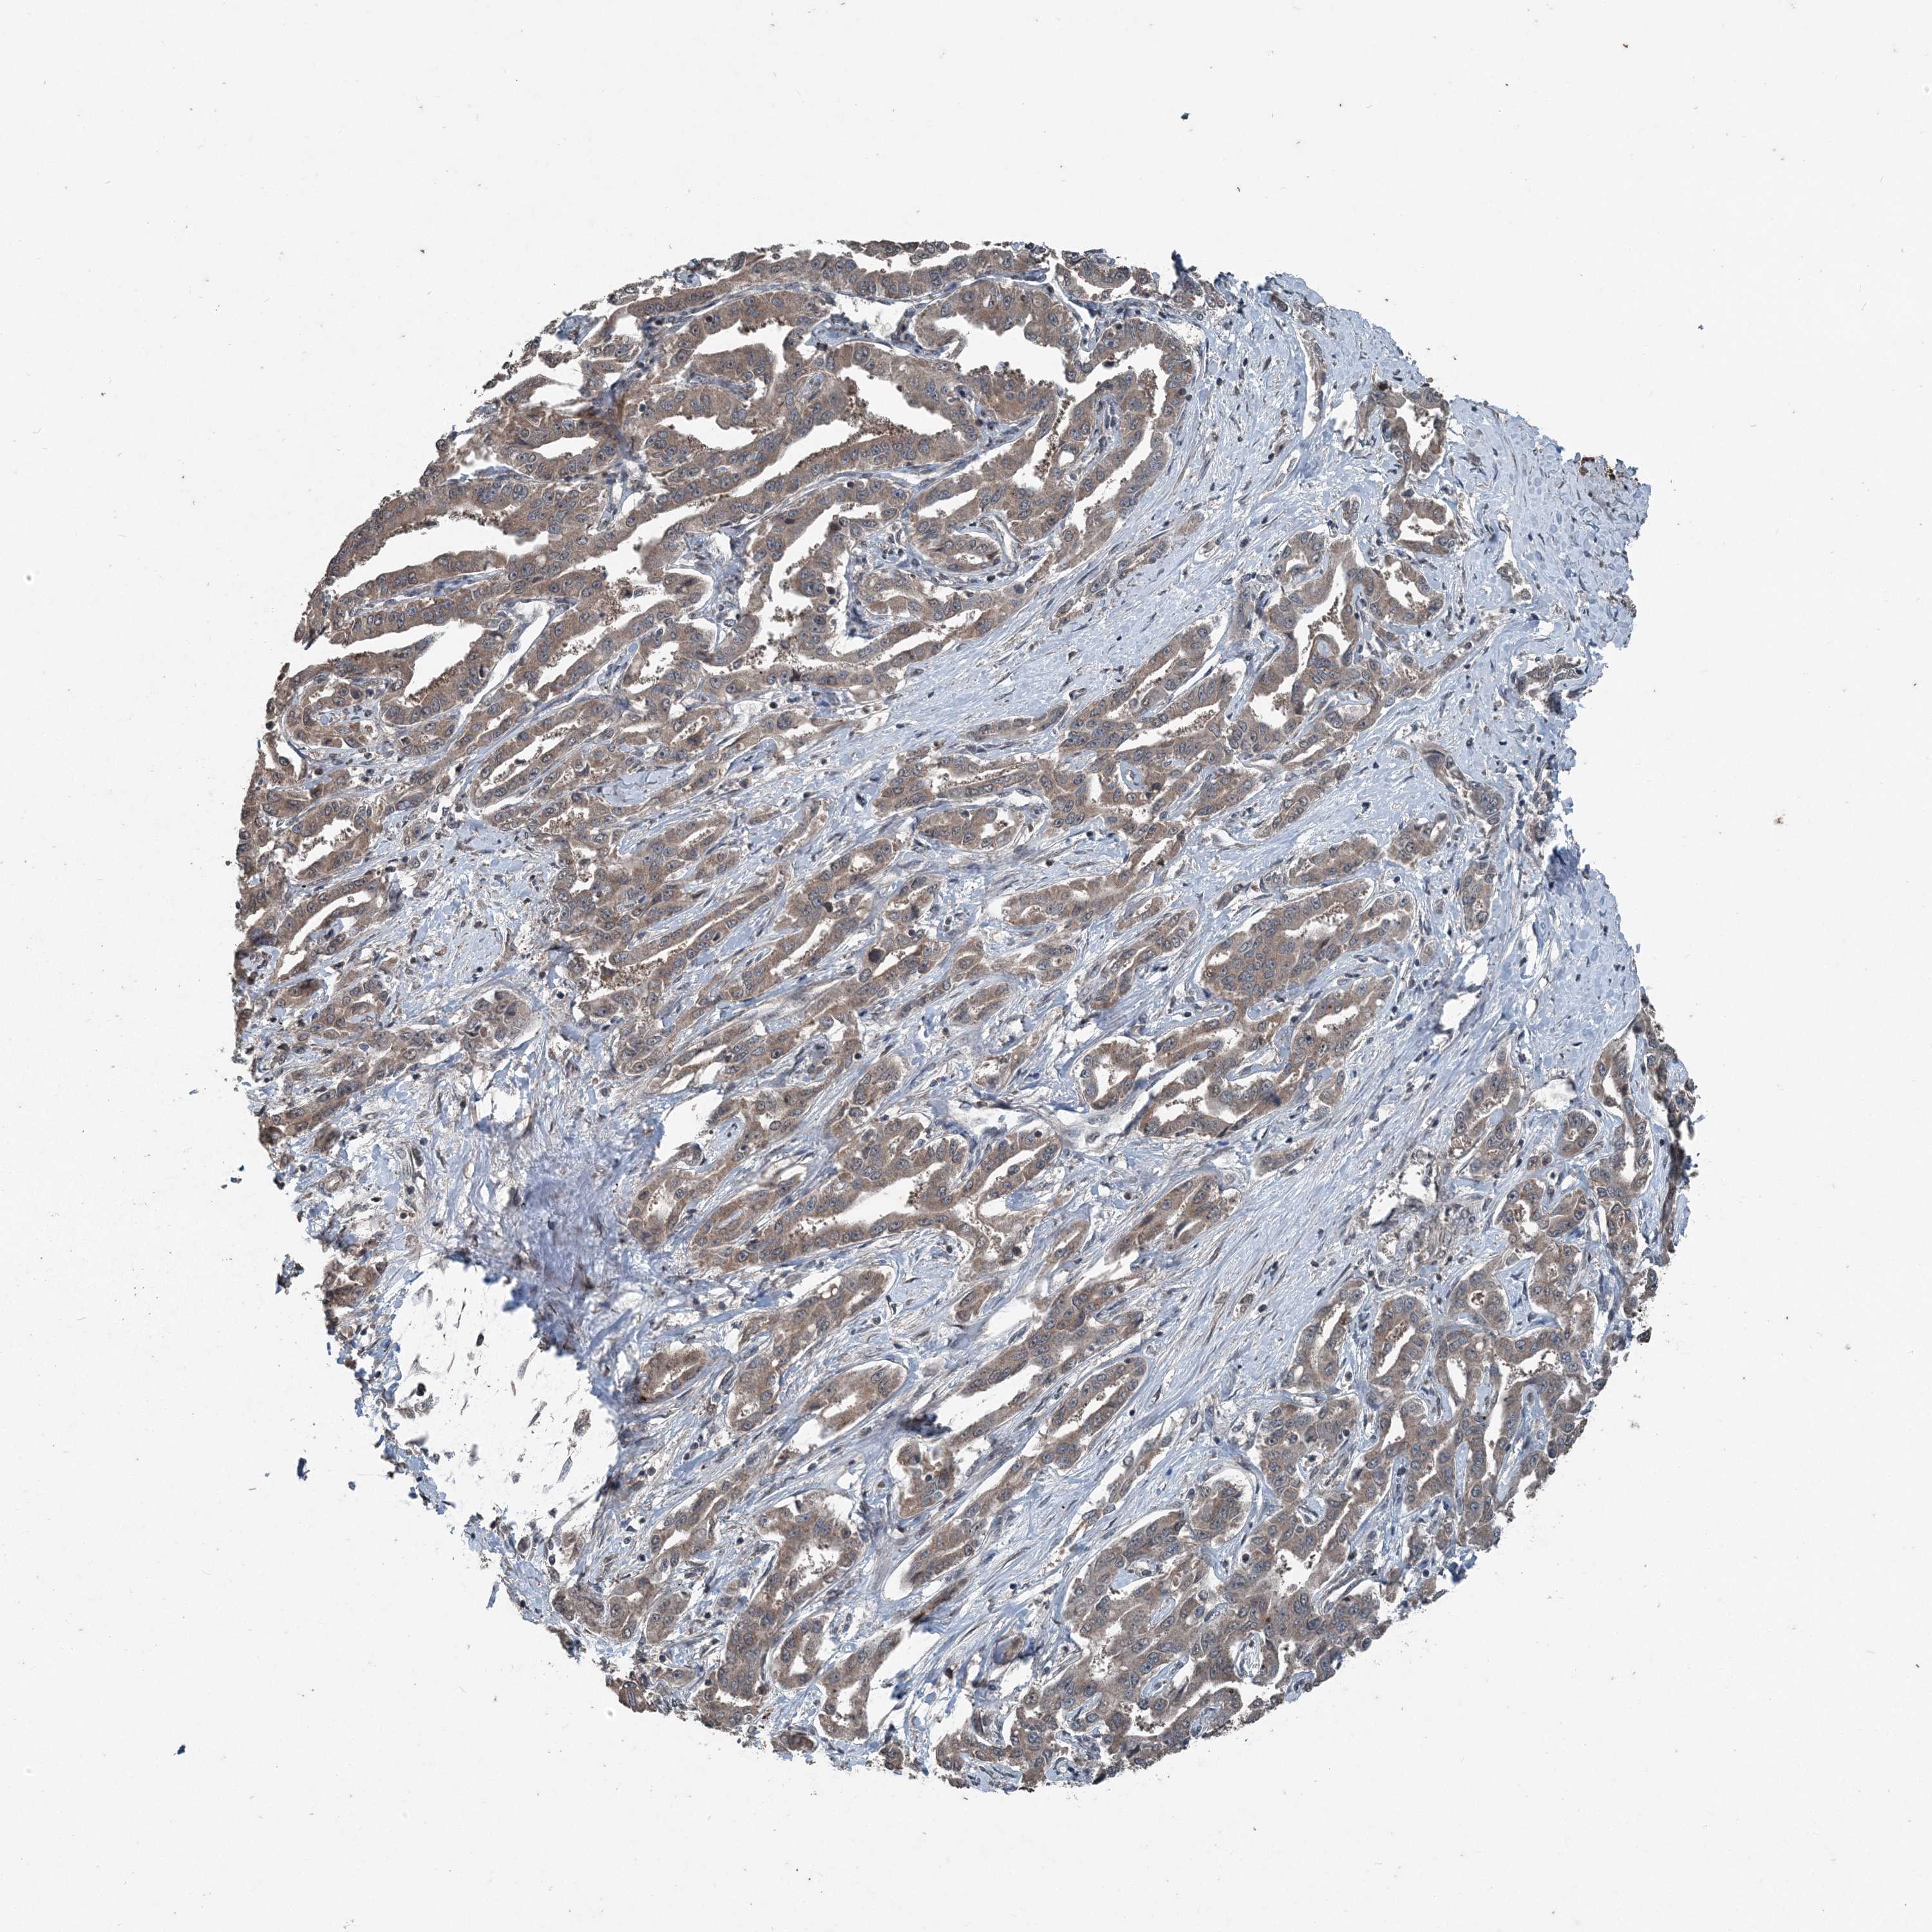

LIVER CANCER - Protein expressioni

A mouse-over function shows sample information and annotation data. Click on an image to view it in a full screen mode. Samples can be filtered based on level of antibody staining by selecting one or several of the following categories: high, medium, low and not detected. The assay and annotation is described here.

Note that samples used for immunohistochemistry by the Human Protein Atlas do not correspond to samples in the TCGA dataset.

Antibody stainingi

Antibody staining in the annotated cell types in the current human tissue is reported as not detected, low, medium, or high, based on conventional immunohistochemistry profiling in selected tissues. This score is based on the combination of the staining intensity and fraction of stained cells.

Each image is clickable and will lead to virtual microscopy that enables deeper exploration of all samples and also displays staining intensity scores, fraction scores and subcellular localization as well as patient and tissue information for each sample.

Cholangiocarcinoma

Carcinoma, Hepatocellular, NOS